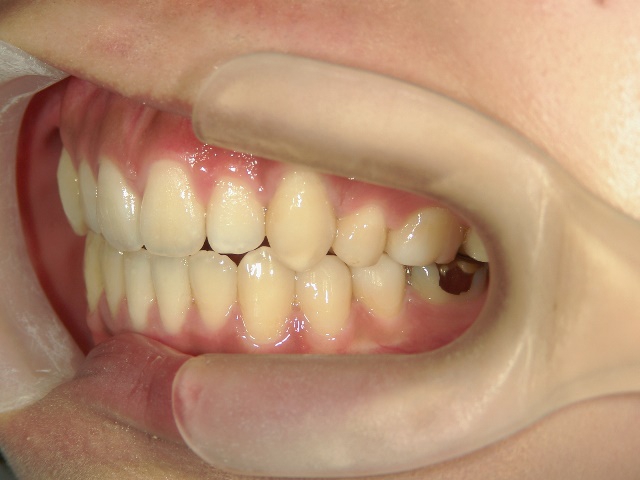

主訴:奥歯で噛んだときに前歯が噛み合わない

高校時代には、歯並びを改善しようと様々な矯正サイトを閲覧し、自分自身が開咬であることを知りました。開咬とは、上下の歯を噛み合わせた時に前歯に隙間ができることを言います。そういえば、麺を前歯で噛みきること、ハンバーガーにガブッと噛みつくことができませんでした。

2年を少し過ぎたころには歯並びが良くなり、開咬もだいぶ改善されました。結婚式を予定していたため早期終了をさせていただきましたが、開咬が治ってハンバーガーをガブッと噛みきることができるようになって、とっても嬉しいです。式でもきれいな歯並びで、思いっきり笑うことができました。